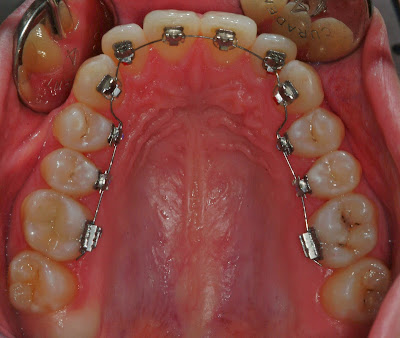

Ganz kurz zur Behandlung: meine Zahnfehlstellungen werden mit einer festen Zahnspange in Lingualtechnik behoben. Das heisst, dass die Zahnspange von aussen nicht sichtbar ist, da die Brackets auf der "Zungenseite" - also von hinten - auf die Zähne geklebt werden.

Zum Schluss noch Bilder meines Gebisses, damit ihr euch alles besser vorstellen könnt: